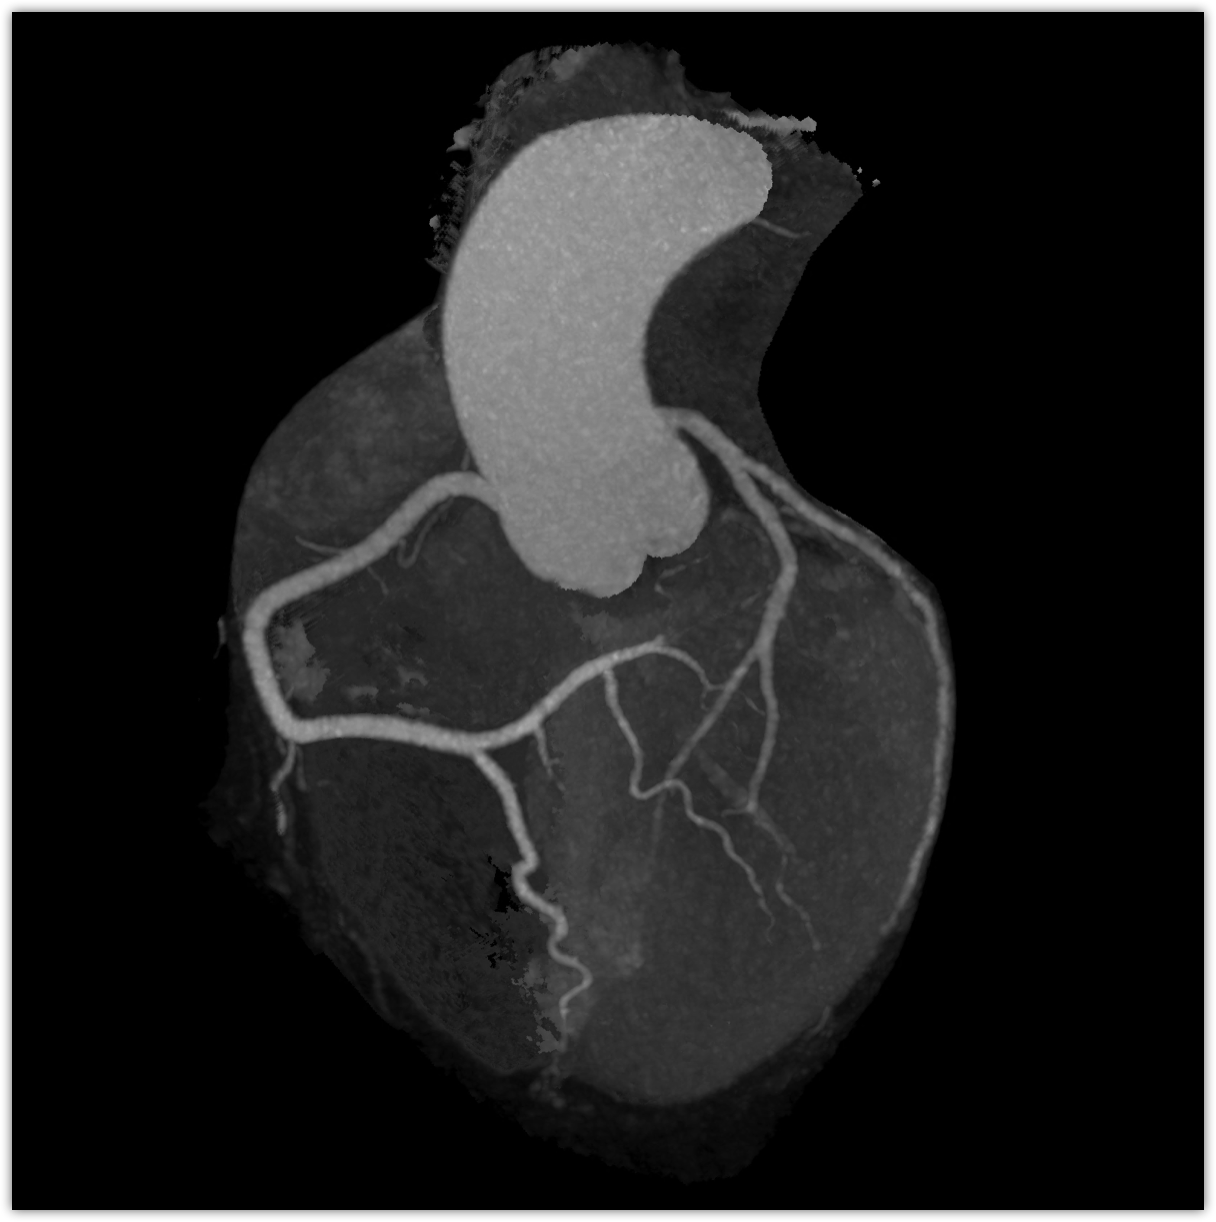

We believe in keeping you as healthy as possible. One of the ways we do this is by checking for heart disease with a Coronary CT Angiogram (CCTA) — a non-invasive scan that can see disease in your heart vessels even if you have no symptoms.

Most people have no symptoms until it’s too late. A Coronary CT Angiogram (CCTA) lets us see disease in the vessels of your heart — before a heart attack happens.

Coronaries scan